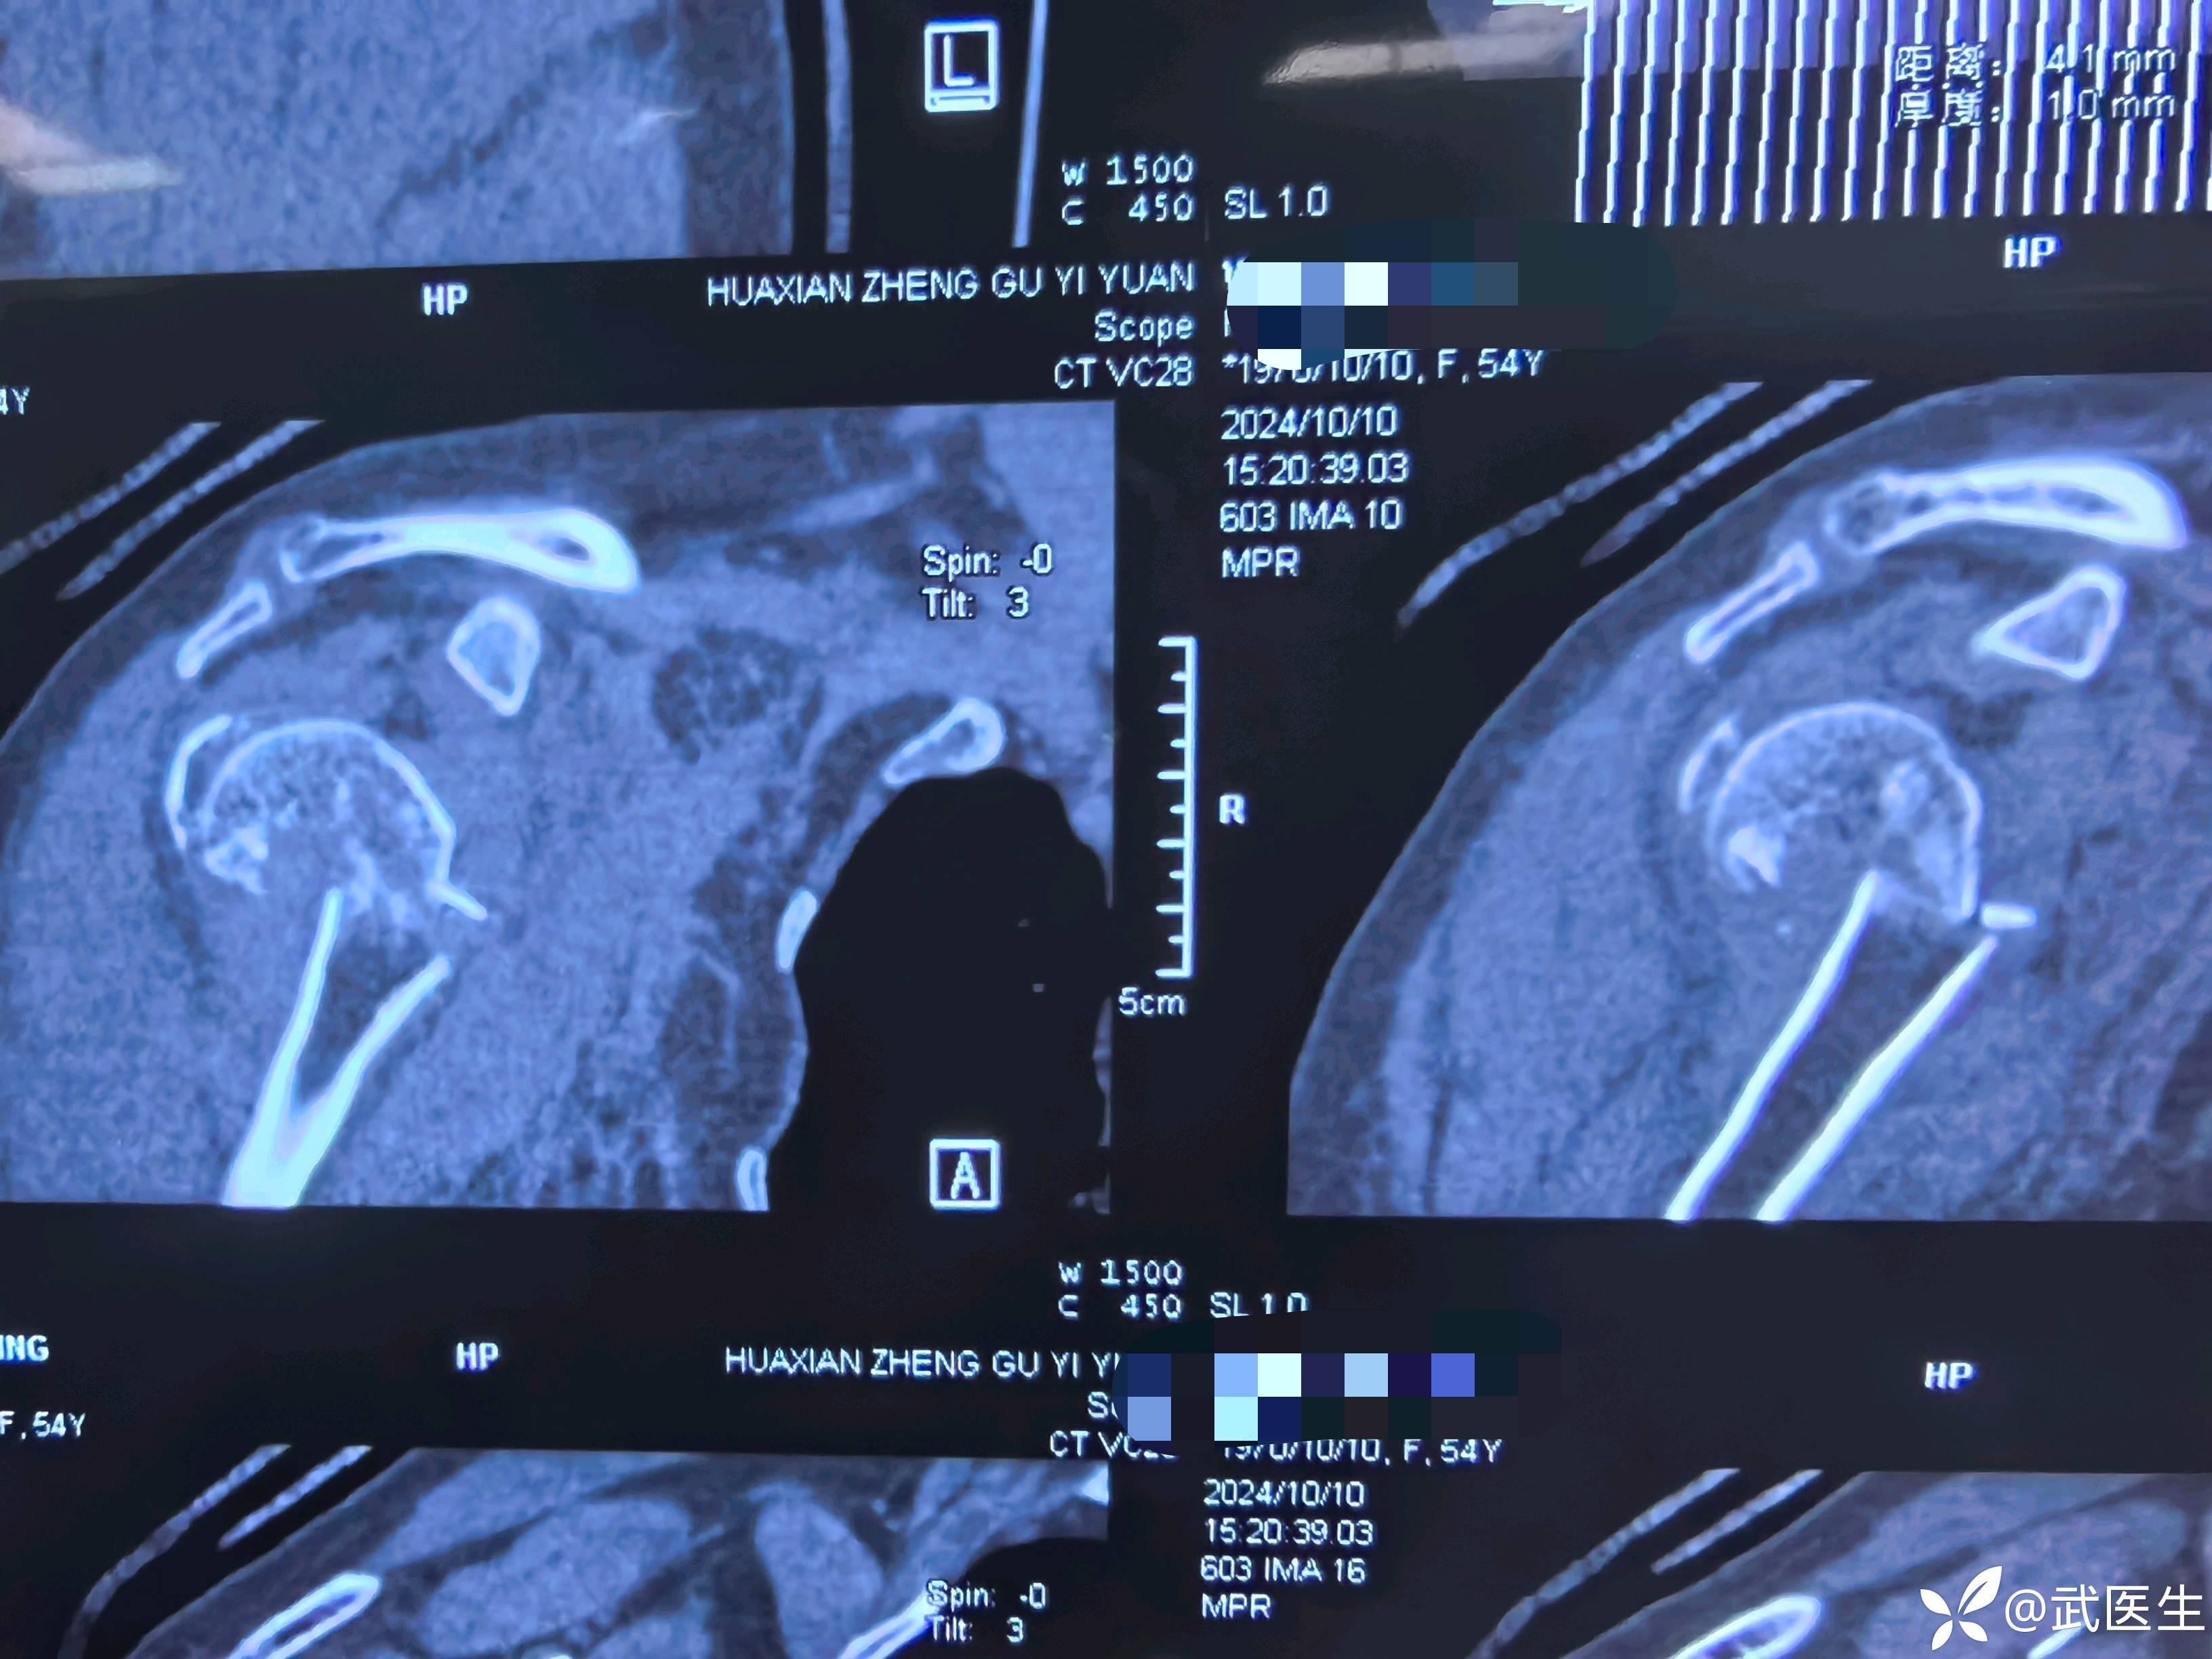

术中透视复位良好,术后CT验证一下

术后两周内外展枕维持,主动肩关节钟摆样活动,两周后主动外展功能锻炼,期待有个不错的肩关节功能,后期随访再发。